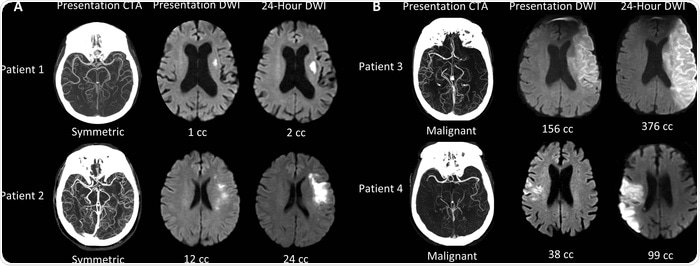

We are creating a machine learning algorithm that can identify LVO patients with symmetric collateral circulation that is a marker of small cores that are growing slowly. This is one of several algorithms that we are combining into a suite of algorithms that are capable of capturing all of the key information for the evaluation of the acute stroke patient.

It turns out that the growth of the ischemic core varies widely amongst patients. Our research, confirmed by work at other centers, shows that nearly half of all patients have a slow growth pattern and may be treated 24 hours after stroke onset, and perhaps even later.

The great variation in the growth of the ischemic core in patients with LVO is due to differences in the collateral circulation. The collateral circulation are arteries that provide blood to parts of the brain that are endangered.

The collaterals come from other large arteries that are not occluded. The variation in collateral blood flow is extraordinarily large, and because of that, the growth of ischemic cores is also very different from patient to patient.